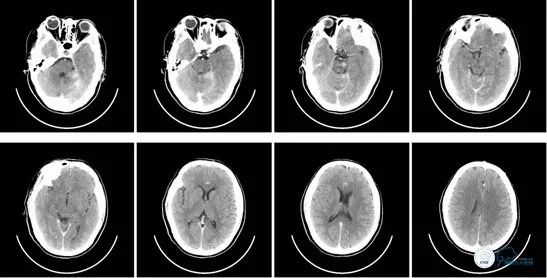

术后即刻头颅CT:可见少量造影剂渗出,排除术后出血。

图12

术后8小时头颅CT: